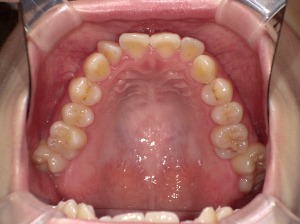

歯列のアーチとは、上・下の歯が並んでいるカーブの形のことです。

上から見たとき、歯が半円状に並んでいる様子をイメージしてください。

| 楕円型 | 自然でバランスの良い形 | 多くの人の理想的な歯列形状 |

矯正治療では、歯並びだけでなくアーチ形状そのものをコントロールすることが可能です。